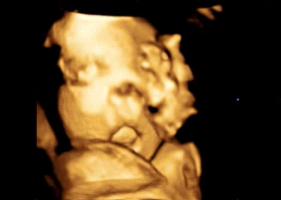

ps.사진은 입체초음파에서 하품할때 찍힌영상인데

너무귀여워서 올려봐요ㅋㅋ제 뱃속에서 소변도 보고 딸꾹질에 하품도 하고 너무 신기해요

귀여워라~~ 하품을 하다니♡